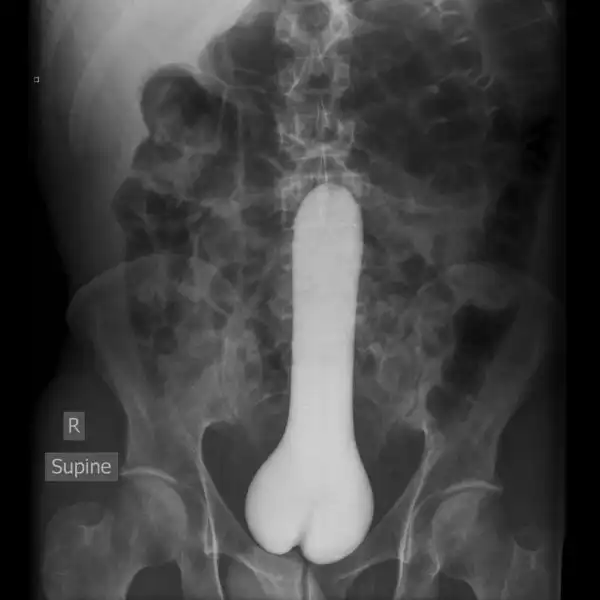

Врачебные находки в интимных местах

Или как впихнуть невпихуемое :lol: